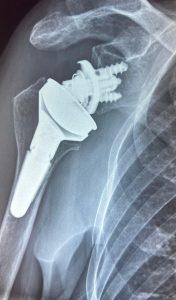

A differenza della protesi anatomica tradizionale, la protesi “inversa” inverte la normale anatomia della spalla.

- Nella protesi inversa: la “palla” viene fissata alla scapola e la “coppa” all’omero.

Questa inversione meccanica dei rapporti articolari permette al muscolo deltoide di sollevare il braccio anche quando i tendini della cuffia dei rotatori sono completamente rotti o assenti.